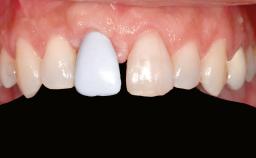

A 20-year-old woman was referred for implant therapy in 2004. Her medical history revealed no significant findings, and neither did she smoke nor take any medications. An extraoral examination revealed no abnormalities of the skin, hair or nails. The intraoral examination revealed only 11 permanent teeth clinically. These were normal in shape, size, and color. In addition, eight retained deciduous teeth (53, 62, 63, 71, 72, 73, 81, 82) were present. No abnormalities were detected during the general examination. The family history revealed that the patient’s father and two sisters were on record with similar conditions. The clinical examination revealed a thick gingival biotype. No recession of the attached gingiva was noted, but the retained deciduous teeth were mobile and unsightly. As a syndrome had not been diagnosed, the case was categorized as non-syndromic oligodontia.

Prosthesis Type FDP